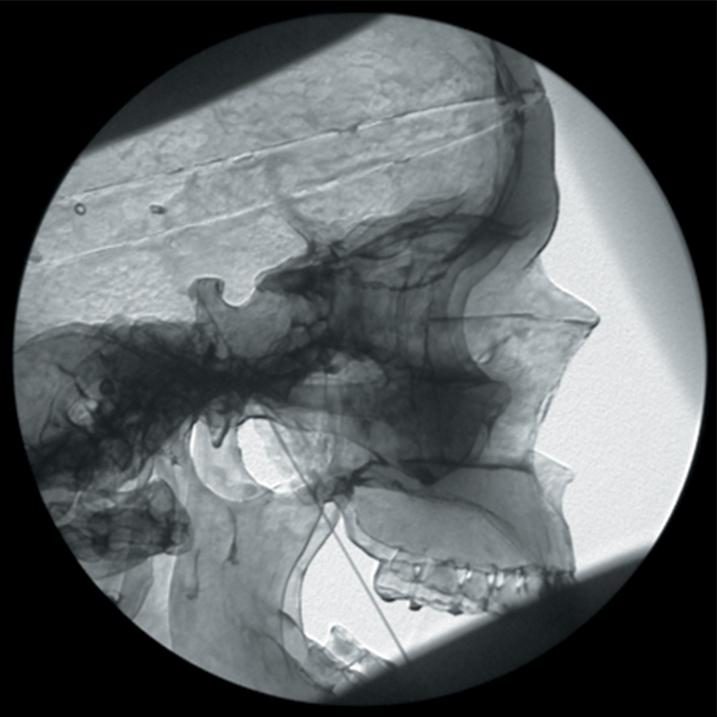

The Regional Anaesthesia Simulation Manikin has been designed by a Consultant Anaesthetist at the Manchester and Salford Pain Centre for training anaesthetists in correct needle placement in Nerve Blocks for pain management.

- Orientation of image and identification of appropriate radiographic landmarks

- Identification point of needle insertion and angle of direction

- Recognition of contact with deep bony structures

- Principle of withdrawing and directing needle to alter the angle

- The end point of simulation is the correct radiographic appearance

- Trigeminal ganglion block or radiofrequency needle placement

- The manikin consists of a specially coated plastic human skeleton, head covered in artificial skin and fabric covered torso, on which trainees can practice the placement of needles under X-ray image intensifier control

- The X-ray density of the manikin is low so that the doses of radiation used during simulated procedures are reduced